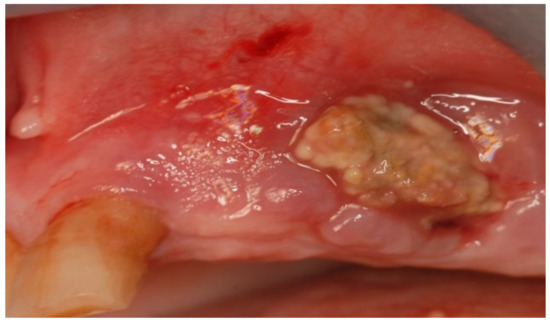

3.1. Clinical Case 1

3.2. Clinical Case 2

3.3. Clinical Case 3

3.4. Clinical Case 4

3.5. Clinical Case 5

3.6. Clinical Case 6